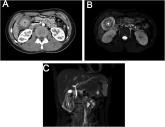

ArticleWhat's your diagnosis?Author:Jiayu Yan, MDPublish date: July 13, 202315-year old girl with history of upper quadrant pain.Read More